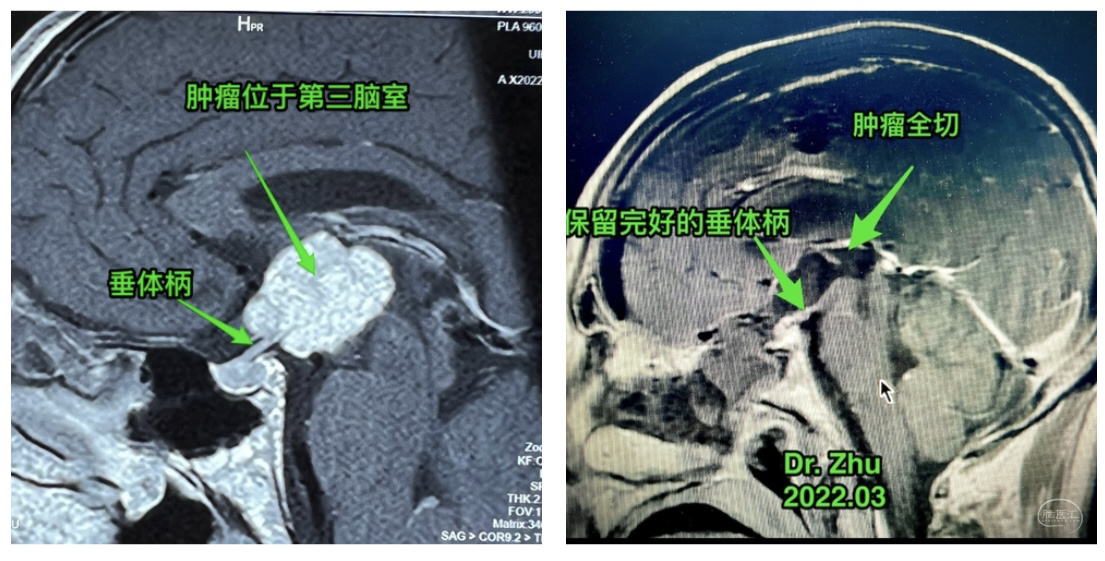

术前

术后